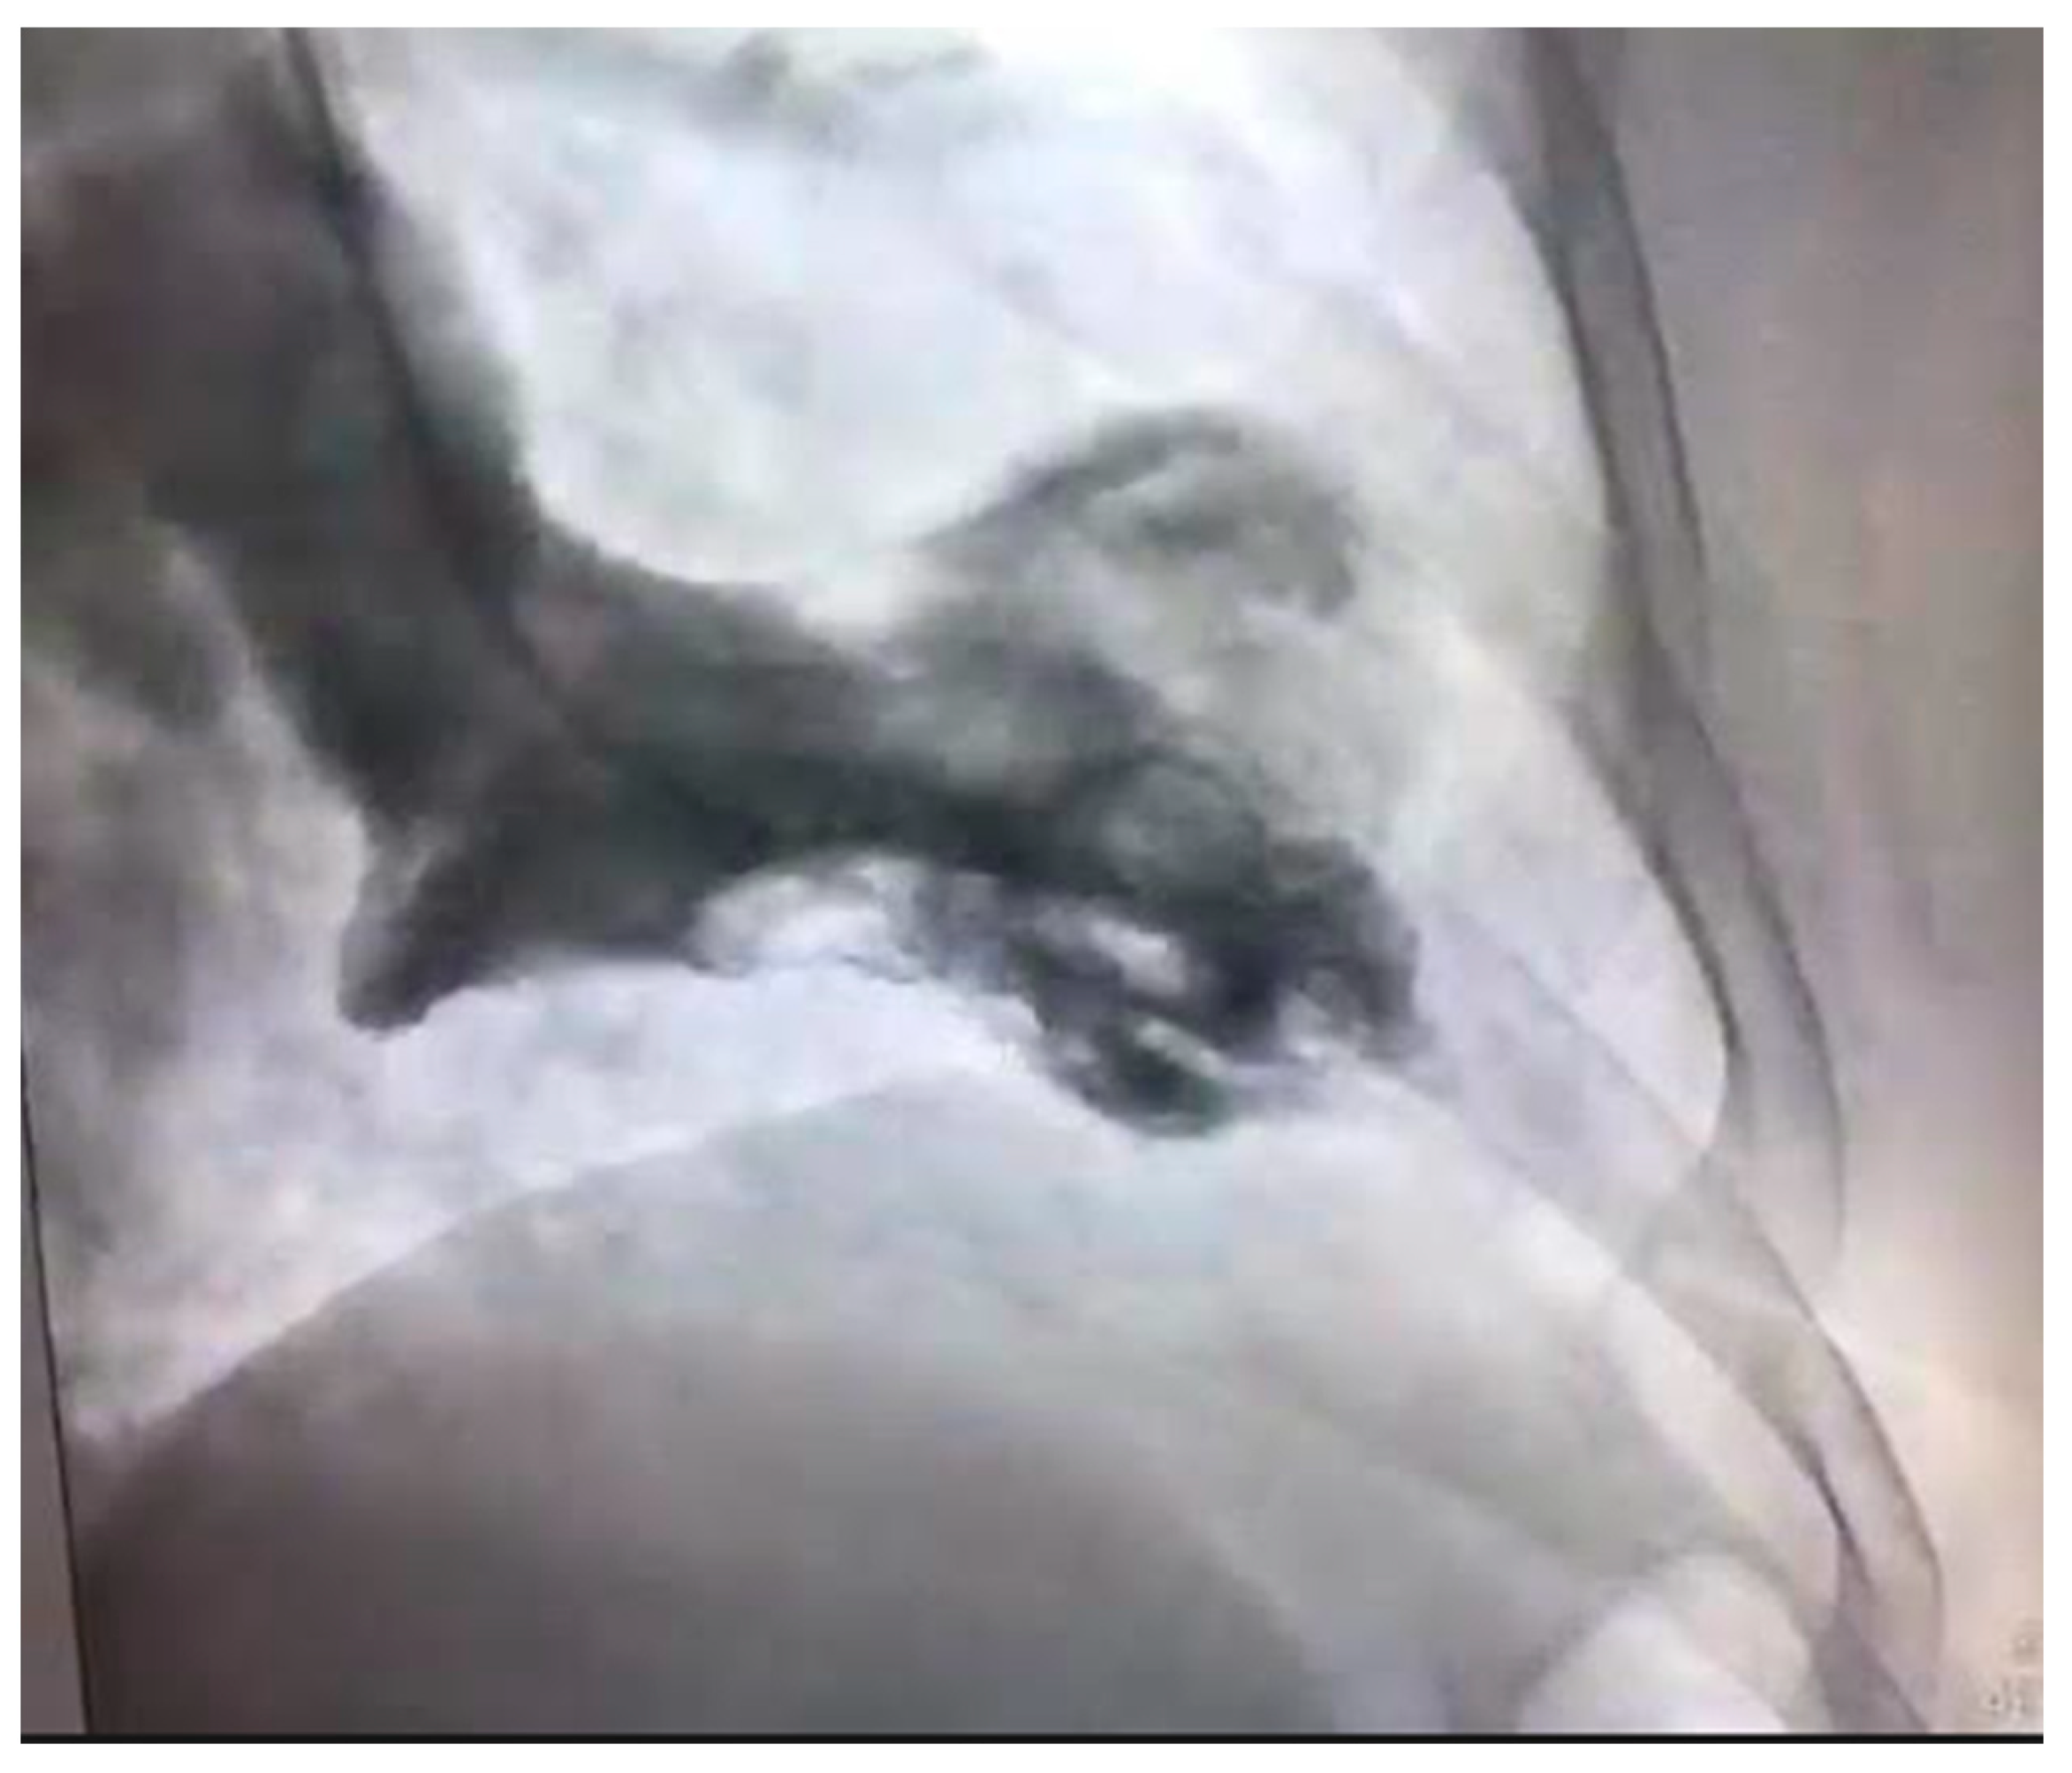

4.4. Spontaneous Coronary Artery Dissection

- Hayes, S.N.; Kim, E.S.; Saw, J.; Adlam, D.; Arslanian-Engoren, C.; Economy, K.E.; Ganesh, S.K.; Gulati, R.; Lindsay, M.E.; Mieres, J.H.; et al. Spontaneous Coronary Artery Dissection: Current State of the Science: A Scientific Statement From the American Heart Association. Circulation 2018, 137, e523–e557. [Google Scholar] [CrossRef] [PubMed] [Green Version]